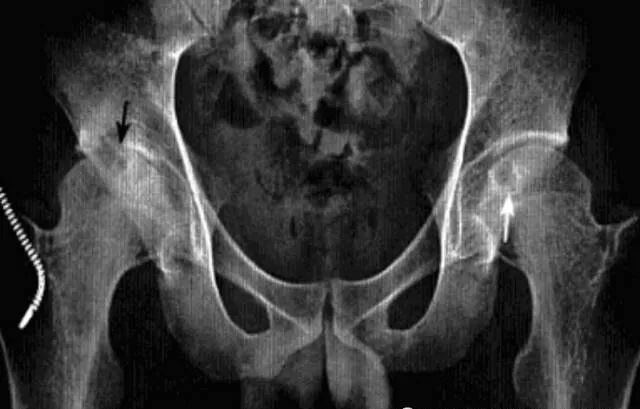

强直性脊柱炎累及髋关节

系累及中轴骨及近端大关节的血清阴性脊柱关节病。病变对称侵及骶髂关节、椎间小关节、附件韧带和近躯干的大关节,*后导致纤维性或骨性强直和畸形。髋关节是本病*常累及的关节,约占50*。

影像诊断:X线片为主要检查手段,MRI能显示早期髋关节改变。

1、平片:双侧对称受累,早期骨质疏松,关节囊膨隆,股骨头及髋臼骨质侵蚀糜烂;中期关节间隙一致性狭窄,软骨下囊性变,关节面边缘骨质增生,坐骨结节、坐骨耻骨支及股骨大转子可伴骨膜炎;晚期股骨头内移、髋臼内突,关节腔闭锁呈骨性强直。

2、CT:早期少量关节腔积液,可伴髂腰肌囊扩张,同时股骨头骨质疏松,股骨头及髋臼缘囊状、虫蚀状骨质缺损;中期关节面边缘硬化、囊变、骨赘形成,股骨头基底滑膜附着处增生,髋关节间隙均匀一致性狭窄消失,双侧髋对称性骨性强直,股骨头及髋臼可普遍性肥大。

3、MRI:①关节积液,关节间隙增宽,②滑膜增厚,增强后明显强化,③关节软骨水肿,④关节面软骨信号改变,炎性血管翳增生,信号强度不均,⑤软骨下囊性变,⑥关节骨性强直。